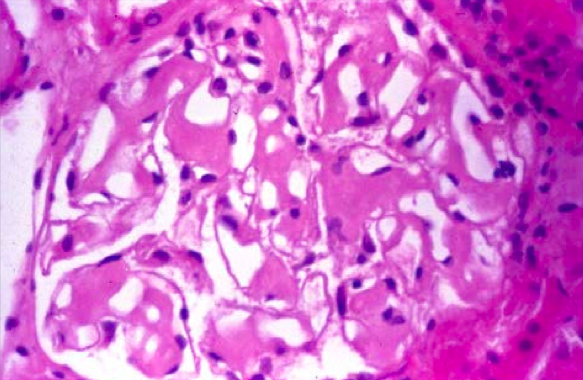

Amyloid deposition in the GI tract can cause malabsorption. Deposition in the heart can cause arrhythmias, cardiomyopathy and pulmonary edema. High serum protein also increases viscosity and can cause ischemic damage. Hypoalbuminemia, renal insufficiency and proteinuria are due to renal nephrotic syndrome from amyloid disrupting the glomerular basement membrane (shown below, note that amyloid deposition does not induce an inflammatory response).

Note the grayish, glistening material that is nodular, patchy and dispersed. This is amyloid deposition in the heart. On histology you see an extracellular, amorphous, pale, pink material. You would see atrophy of the surrounding cells. On immunohistochemical staining with Congo red you see apple-green birefringence.